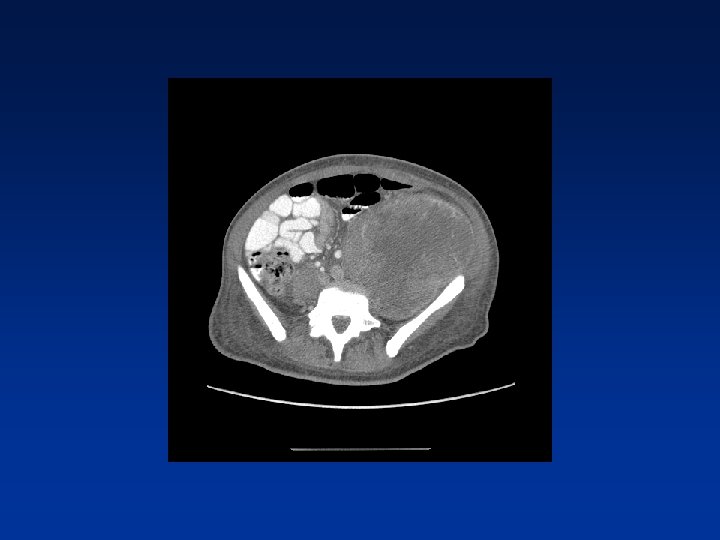

CASE